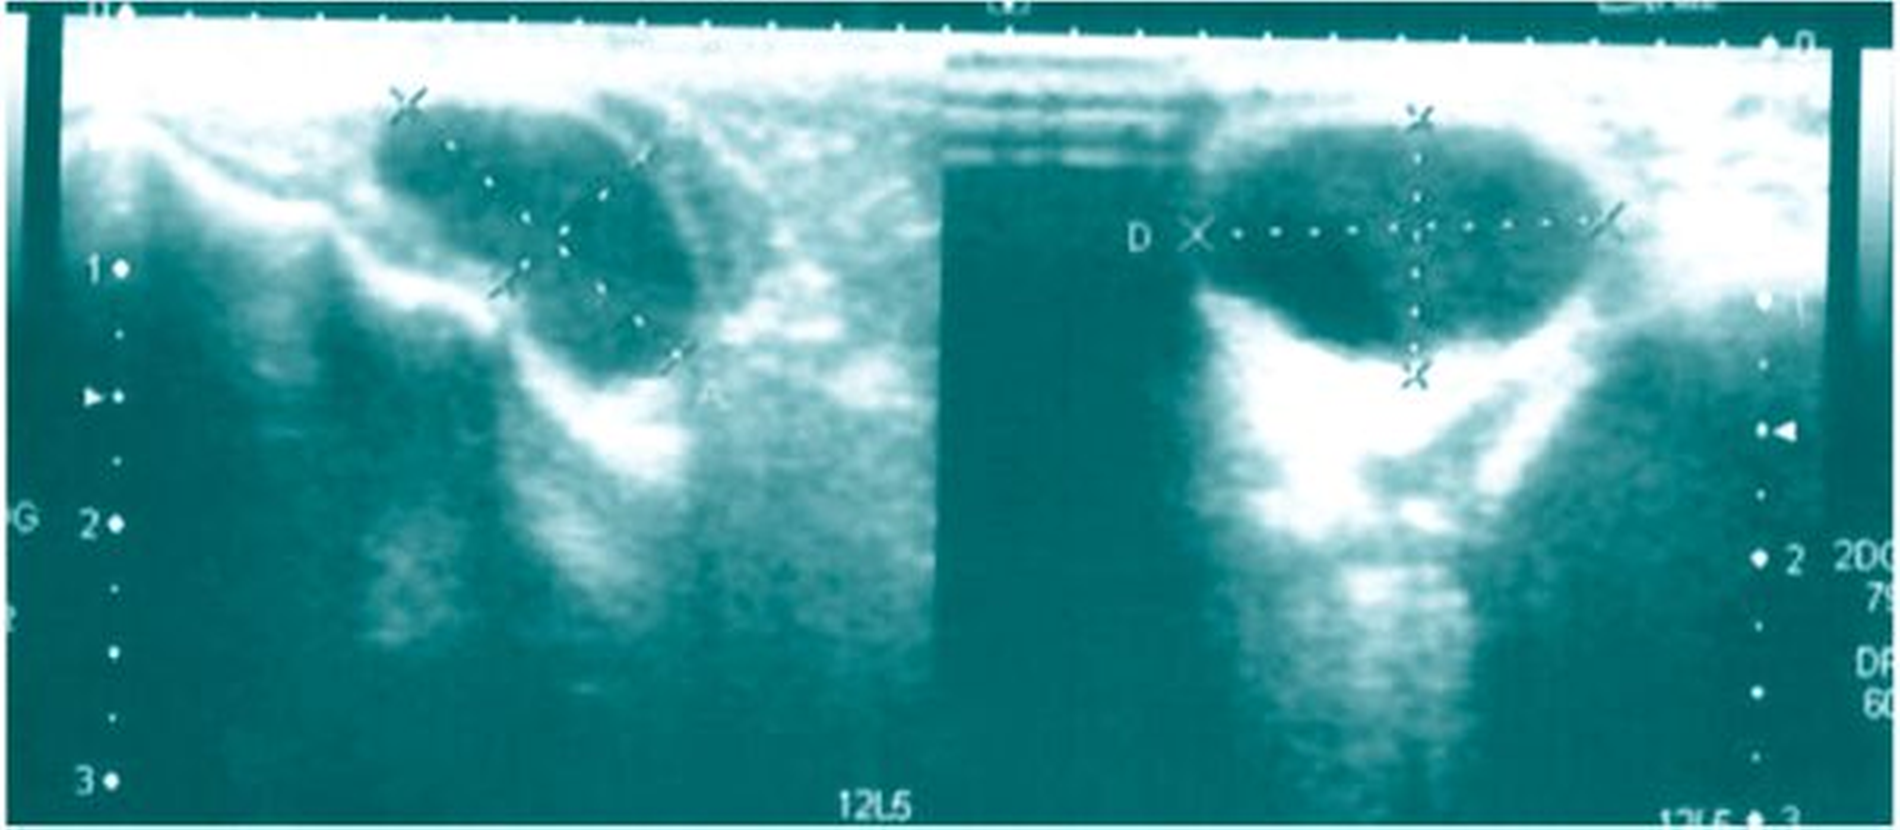

Bei der Inspektion ließen sich keine Auffälligkeiten erkennen, palpatorisch zeigte sich jedoch ein weicher, leicht fluktuierender und zirkulärer Tumor in dem vorbeschriebenen Bereich, der leicht druckdolent und gut verschieblich war. Dental zeigte sich kein Sanierungsbedarf bei einem konservierend und prothetisch suffizient versorgten Restgebiss. Es folgte eine sonografische Untersuchung, in der sich eine 21 mm x 21 mm x 16 mm große, echoarme Raumforderung mit dorsalem Schallschatten im Sinne einer zystischen Veränderung in der rechten Unterlippe darstellen ließ (Abbildung 1).